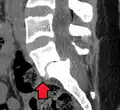

Computed tomography (CT)

Computed tomography can be helpful in evaluating bony vertebral abnormalities, such as fractures.[38] This can be helpful in determining if the fracture is a new, old, and/or progressing fracture.[38] CT use in spondylolisthesis evaluation is controversial due to high radiation exposure.[39]